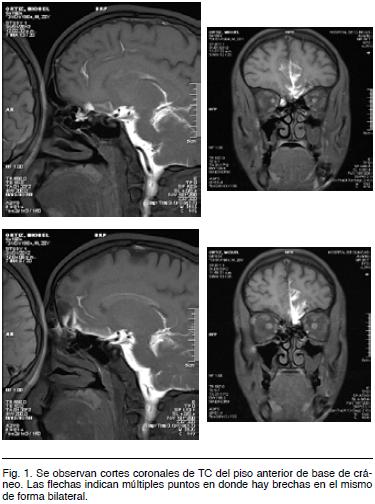

Desde entonces, refiere rinorraquia intermitente por narina izquierda. Se estudia con tomografía computada (TC) (Figura 1) y resonancia nuclear magnética (RMN), siendo enviado para valoración por parte del servicio de Neurocirugía del Hospital de Clínicas.

Es ingresado para estudio, haciéndose una cisterno-RMN. Dado que en nuestro país los equipos de RMN son pocos, tenemos la certeza de que éste fue el primer estudio de cisterno-RMN hecha en Uruguay. El resultado informa dos brechas ósteomeníngeas a nivel del piso anterior de base cráneo, una izquierda y otra derecha (Figura 2).

En el caso clínico analizado se solicito TC y RNM. Al constatar múltiples fracturas en el piso anterior de base de cráneo, quedaron dudas sobre la topografía exacta de la fístula por lo que se decidió realizar una cisterno-RMN. Este estudio fue el primero que se realizó en Uruguay y puso en evidencia dos brechas: una izquierda anterior y otra derecha posterior.